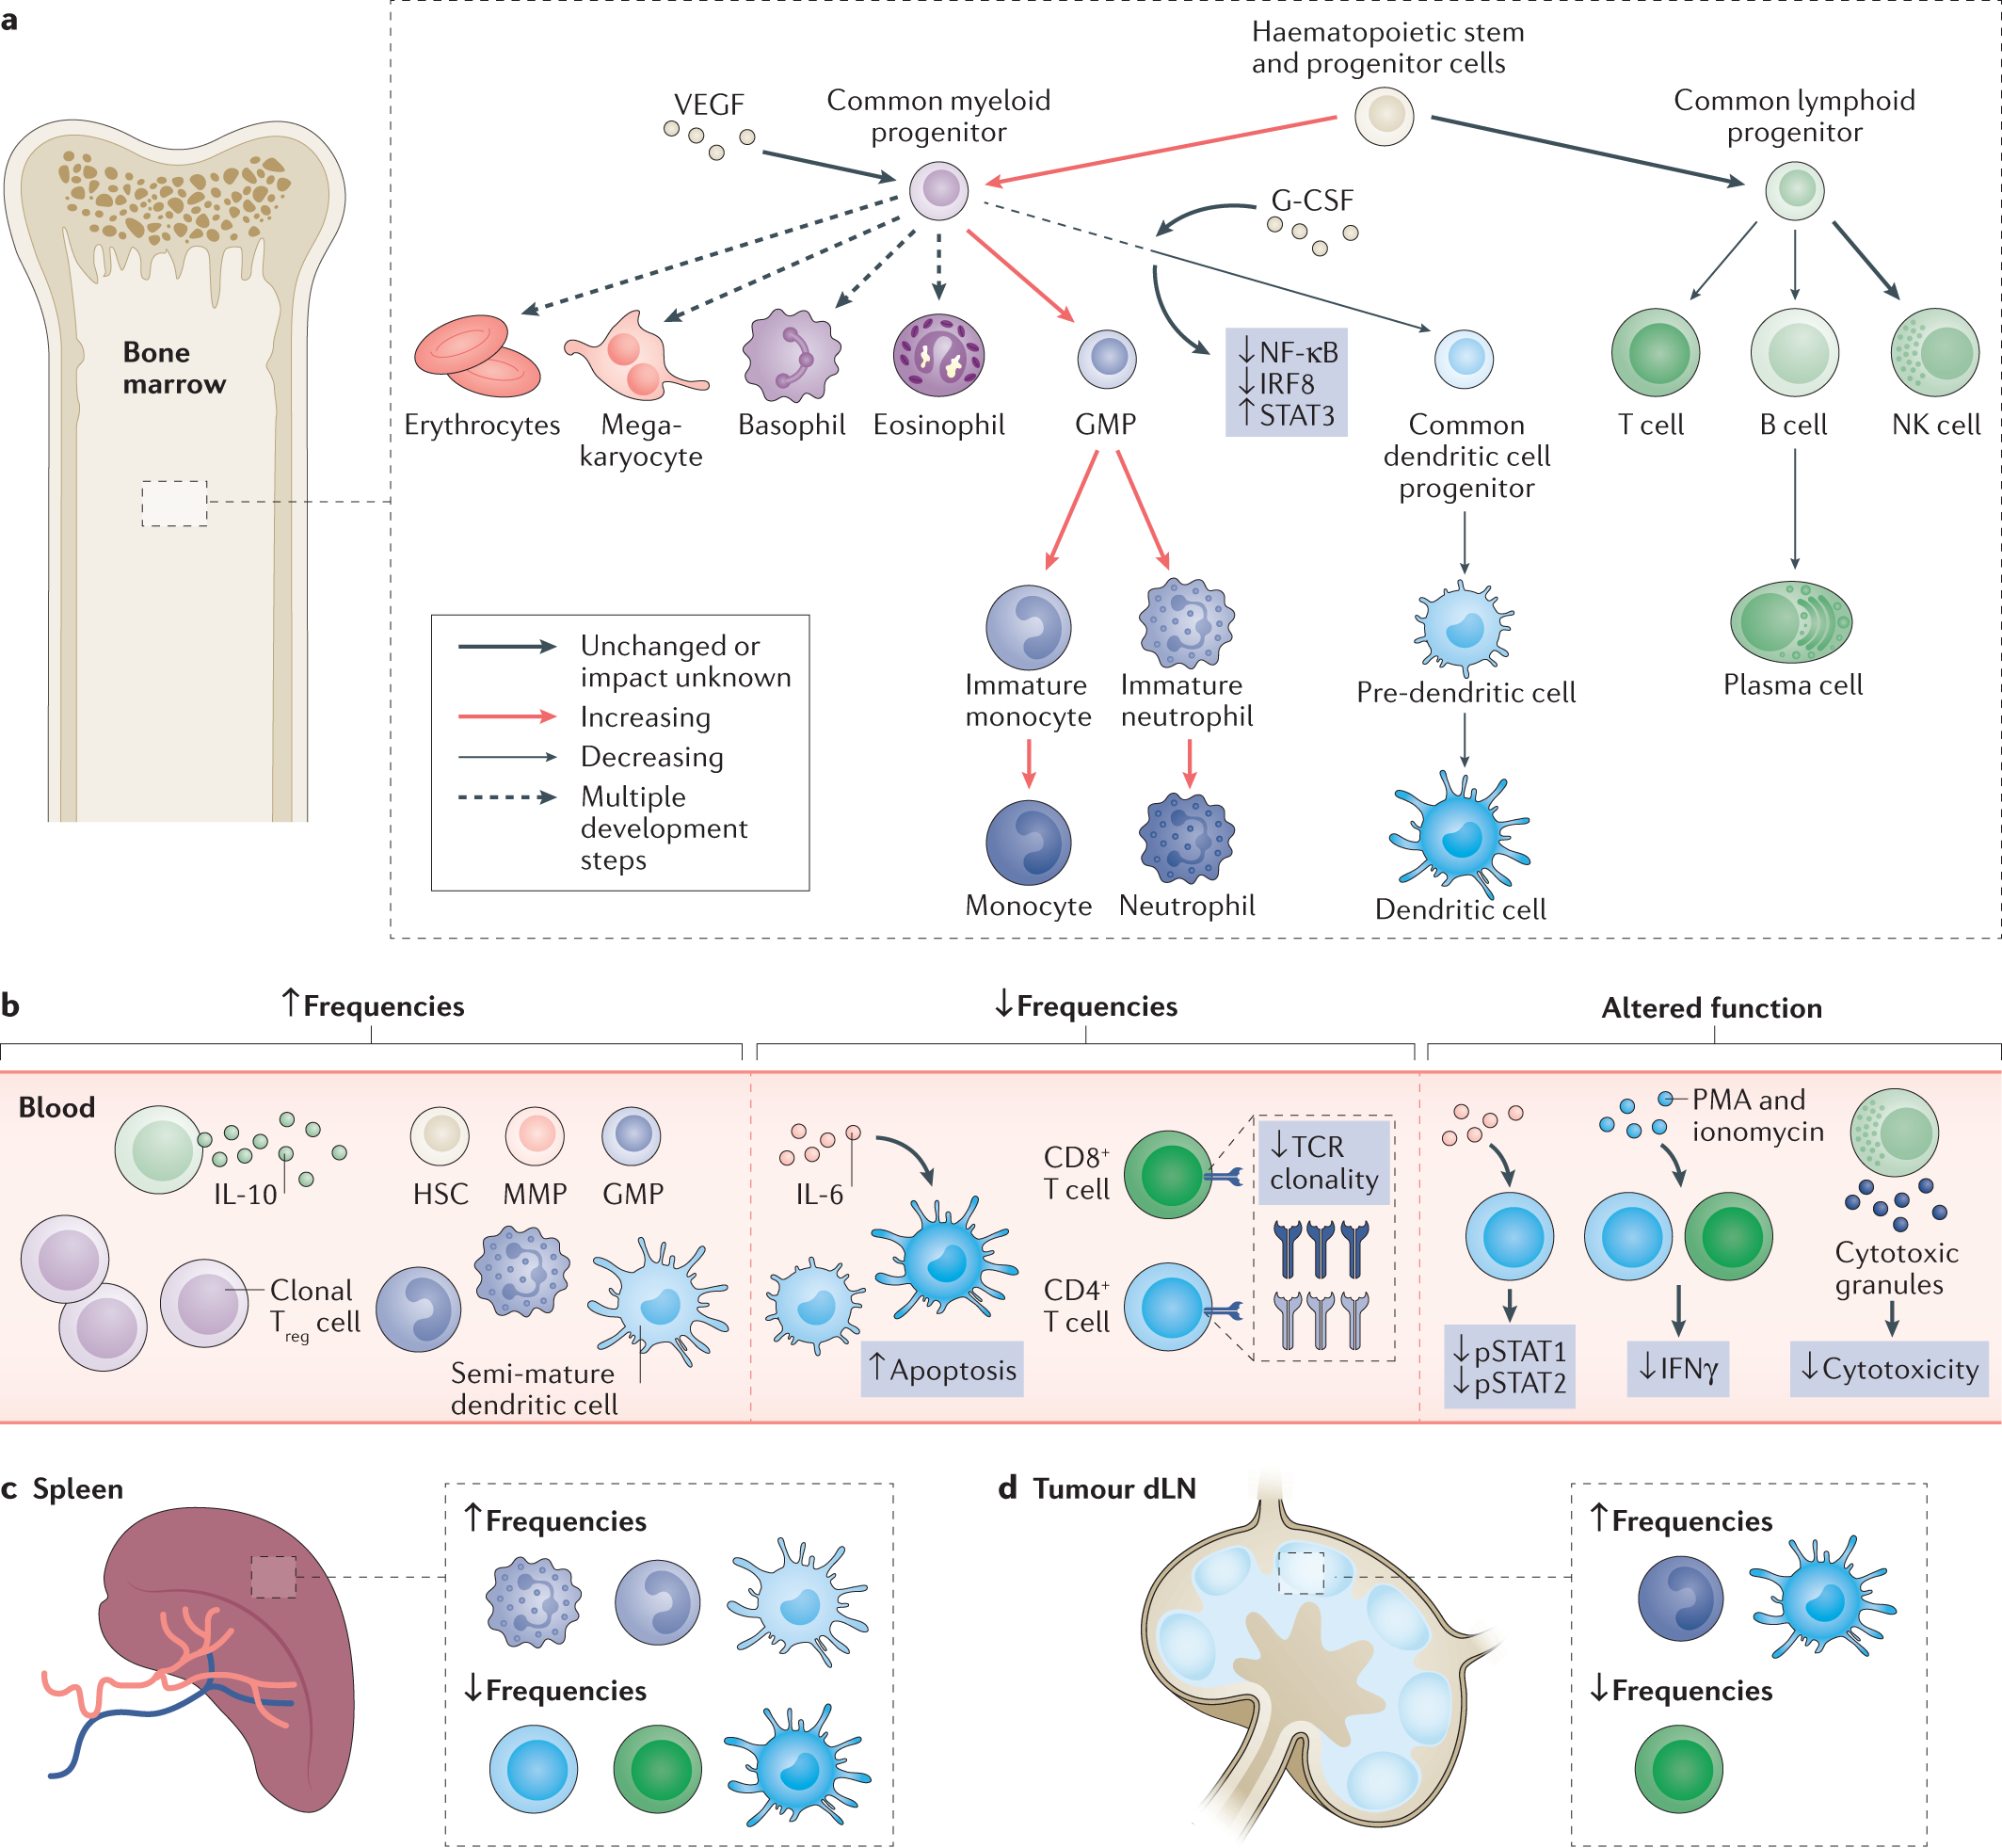

Systemic immunity in cancer